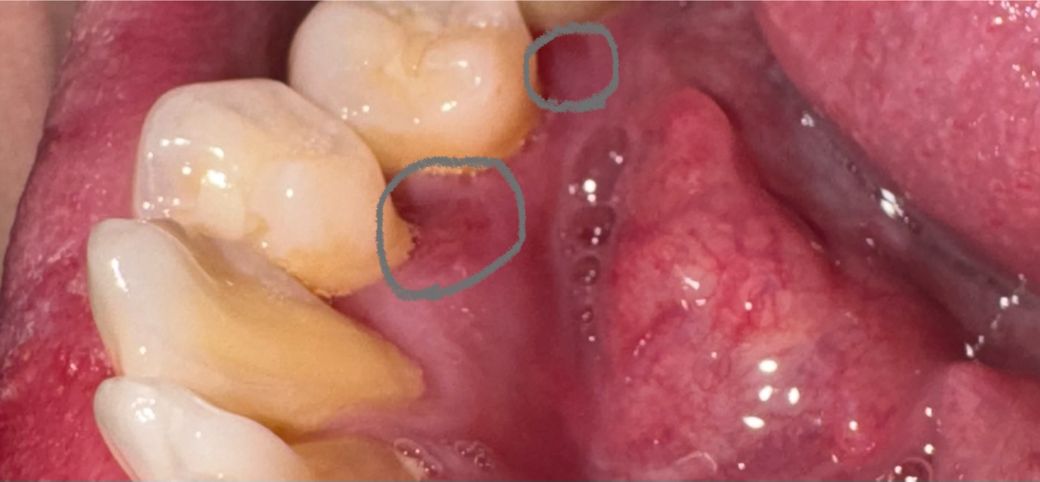

치아안쪽잇몸 상처(까짐)이 일주일정도 지낫는데요.

아래치아 안쪽 잇몸 사진속 동그라미 부분이

일주일전쯤 잇몸이 상처? 까짐?으로 음식물이 닿거나

물마시거나 닿으면 통증이 있었는데 일주일정도 지났는데

지금은 통증은 거의 줄었는데 아직 플래시를 켜고

사진속 부분을 보면 잇몸이 까진건지 상처인지 붉게 아직

남아있는데 저부분 잇몸재생이 원래 일주일지났는데

더 오래 걸릴수도 있나요? 계속 저부분 2곳이 다른 잇몸에

비해 상처난거처럼 붉게 보이는데…혹시나 염증때문이면

치과를 가봐야할까요? 한달전쯤에 치과 건강검진 및 스케일링

치료는 다 했습니다. 의사분들 의견좀 부탁드립니다.

1. 잇몸 상처의 회복은 2주이상 걸리기도 합니다.

2. 지금 올린 사진이 스케일링 후의 사진이라면 꼼꼼하게 양치질 좀 더 잘해주셔야 할 것 같습니다.